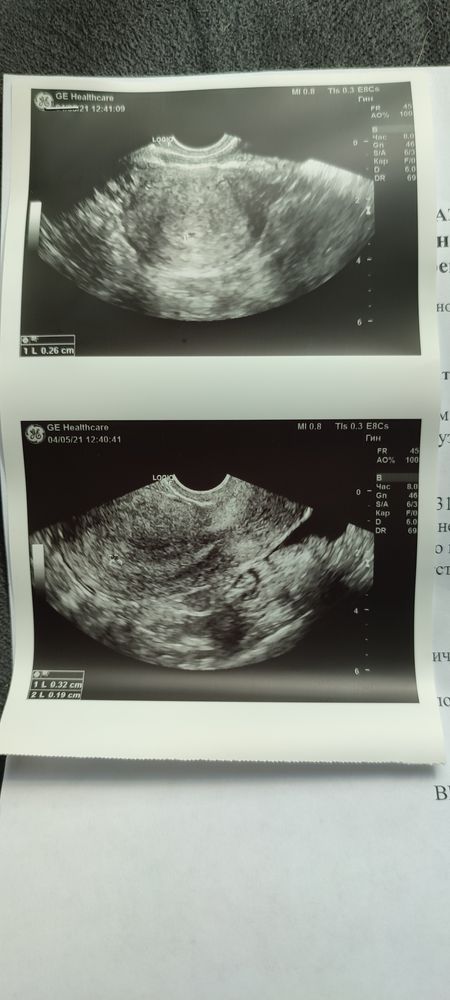

Вчера сдесь спрашивала про УЗИ. Сходила в втоге сделала.Срок ровно 5 недель по М. Вот такая картина...нормально ли это? Врач сказала, что беспокоиться особо не стоит, может была О поздняя. А еще сказала, что мне повезло, что она увидела , так как еще совсем кроха. А О я чувствовала где-то 12 апреля.

Она эмбриональный срок указала по видимому. Акушерский соответствует 5 неделям. Все у вас хорошо😊 очень удивлена ,что разглядели на таком сроке, а так через 2 недельки уже и в плодовом яйце и мелкого можно будет разглядеть )))

У тут все в пределах нормы. На таких малых сроках действительно лишь бы увидели маточную Б, а в остальном потом по срокам разберутся и будет уже более понятно. Она вам тут, видимо, указала эмбриональный срок, потому что в 3 аккушерские недели ничего невозможно увидеть. А если так, то все сопрадает - 5 недель.

Не знаю уже, может своего узиста поменять … очень не нравится уже. Видимо еще с тех слов, что надо девочку,говорю пацана хотим, он, нет, надо помощницу. 🤦♀️ казалось бы, слушай тебе за это деньги платят. Короче у меня 29.03. Были, 29 апреля я уже ходила на узи 6 мм, что Соответвует 3-4 недели. А до этого мне сказали 3 мм и Б под вопросом. Видимо второе узи спецом, чтобы денег больше было, тем более второе узи мимо кассы, он аккуратно к этому подвел... Вас я поздравляю!!! А своего узиста буду менять.